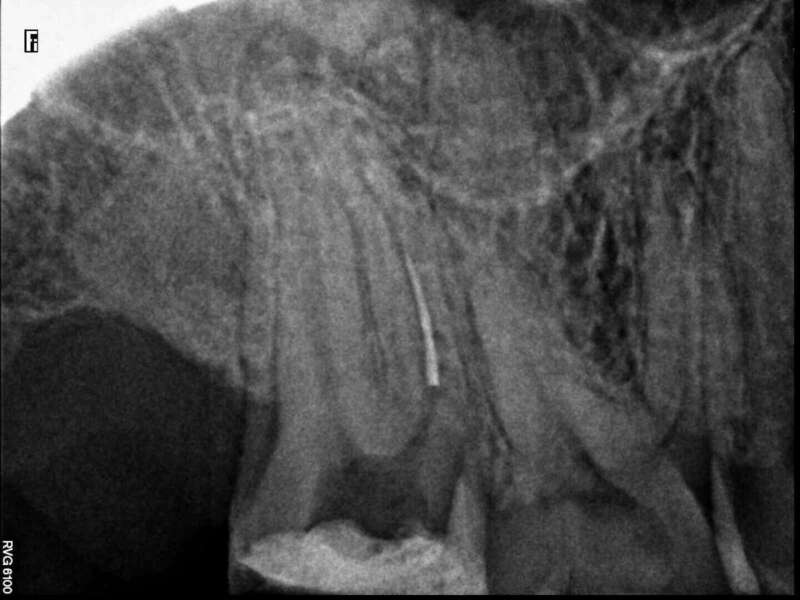

Avant

Après